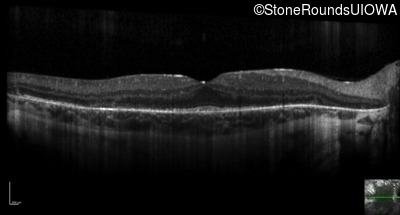

Optical Coherence Tomography - Left - 20/32 -2

Exemplar / OCT Stack

OCT Stack